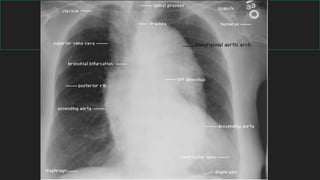

RADIOGRAFIA TORAX

Rx Torax

2 proyecciones

1) Anteroposterior

2) Lateral : Derecha , Izquierda

Generalidades: Rx de tórax

Examen radiológico básico

Frente PA y Perfil

Radiología de tórax normal

Es muy importante realizar una

evaluación sistemática

Se puede seguir cualquier orden

1- Pared torácica

2- Diafragma

3- Pleura

4- Mediastino

5- Hilios y vía aérea

6- Parénquima

Vista panorámica

a- esqueleto torácico

Claviculas

Costillas

Escápula

Columna vertebral

Esternón

- Región situada centralmente

- Límites son:

opérculo torácico (sup.)

diafragma (inf.)

esternón (ant.)

columna vertebral (post.)

BORDE DERECHO

TVBD

VCS

Ao ascendente

TVBDAo ascendente

Aurícula derecha

BORDE IZQUIERDO

TVBI Art.

Subclavia

Botón aórticoTronco de la arteria

pulmonar

Cayado

aórtico

Tronco de la

art. pulmonar

Orejuela de la

aurícula izquierda

Orejuela

aurícula

izquierda

Ventrículo izquierdo

Ventrículo

izquierdo

CORRELACIÓN TOPOGRAFICA

MEDIASTINAL / RX TORAX

Tráquea

- Región central mediastino superior

- Indentación borde aórtico (frente)

Bifurcación traqueal

- Ángulo de bifurcación: 55º - 70º

- Bronquio derecho tiene una

dirección más vertical que el izquierdo